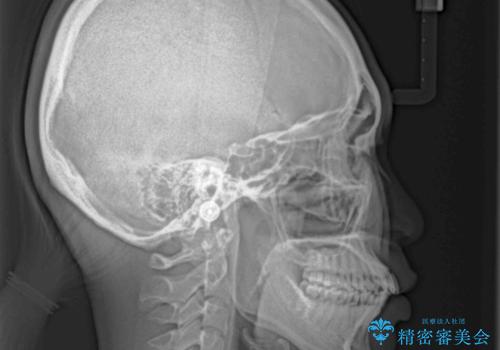

- 全体的なデコボコと口元の突出感を改善したいとのことで来院された患者様です。

このままデコボコを整えるとさらに突出感が増すため、上下左右の第一小臼歯を抜歯し、ワイヤー装置にて矯正しました。